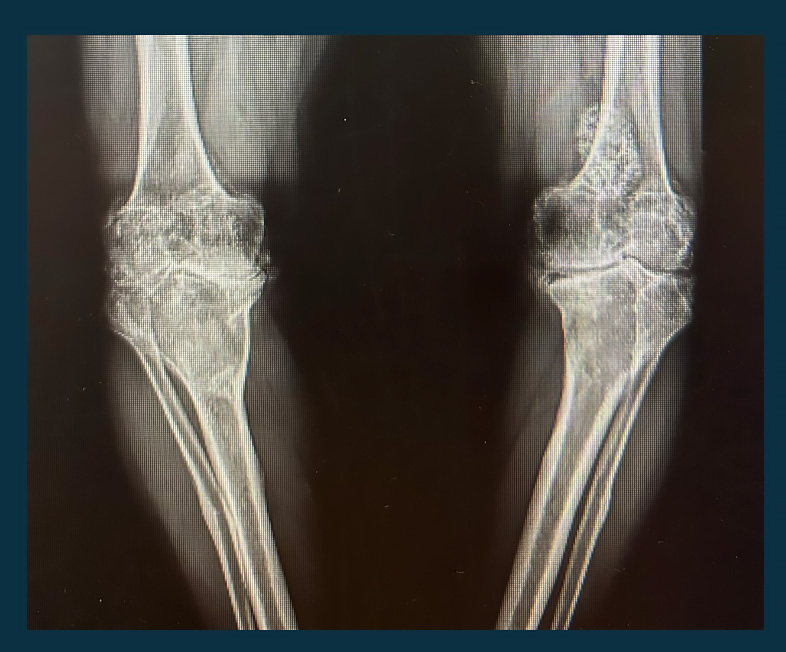

(DİZ EKLEMİ OSTEOARTRİTİ)

Gonartroz, diz eklemindeki kıkırdak dokusunun zamanla aşınması ve dejenerasyonu sonucu ortaya çıkan bir tür eklem hastalığıdır. Bu durum genellikle yaşlanma süreciyle ilişkilidir, ancak bazen genetik faktörler, aşırı kilo, eklem travmaları veya belirli meslekler gibi diğer faktörler de etkili olabilir. Gonartroz, diz ekleminde ağrı, şişlik, sertlik ve hareket kısıtlılığı gibi belirtilerle kendini gösterir.